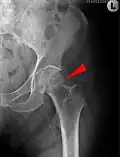

-

Mediale Schenkelhalsfraktur ohne Dislokation -

Laterale Schenkelhalsfraktur mit Adduktions-Dislokation -

Im Vergleich dazu ein gesundes Hüftgelenk